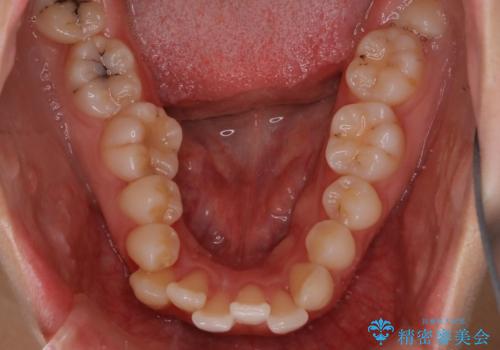

【抜歯インビザ】凸凹を綺麗になおしたい

- 前歯の凸凹を主訴に来院されました。

叢生量が多いため、抜歯が必要となるため、ワイヤー矯正をお勧めしましたが、患者さんの希望によりインビザラインで治療を開始しました。途中でワイヤーリカバリーを必要とせず終了でき患者さんには満足していただけました。

ワイヤー矯正よりも期間がかかっています。